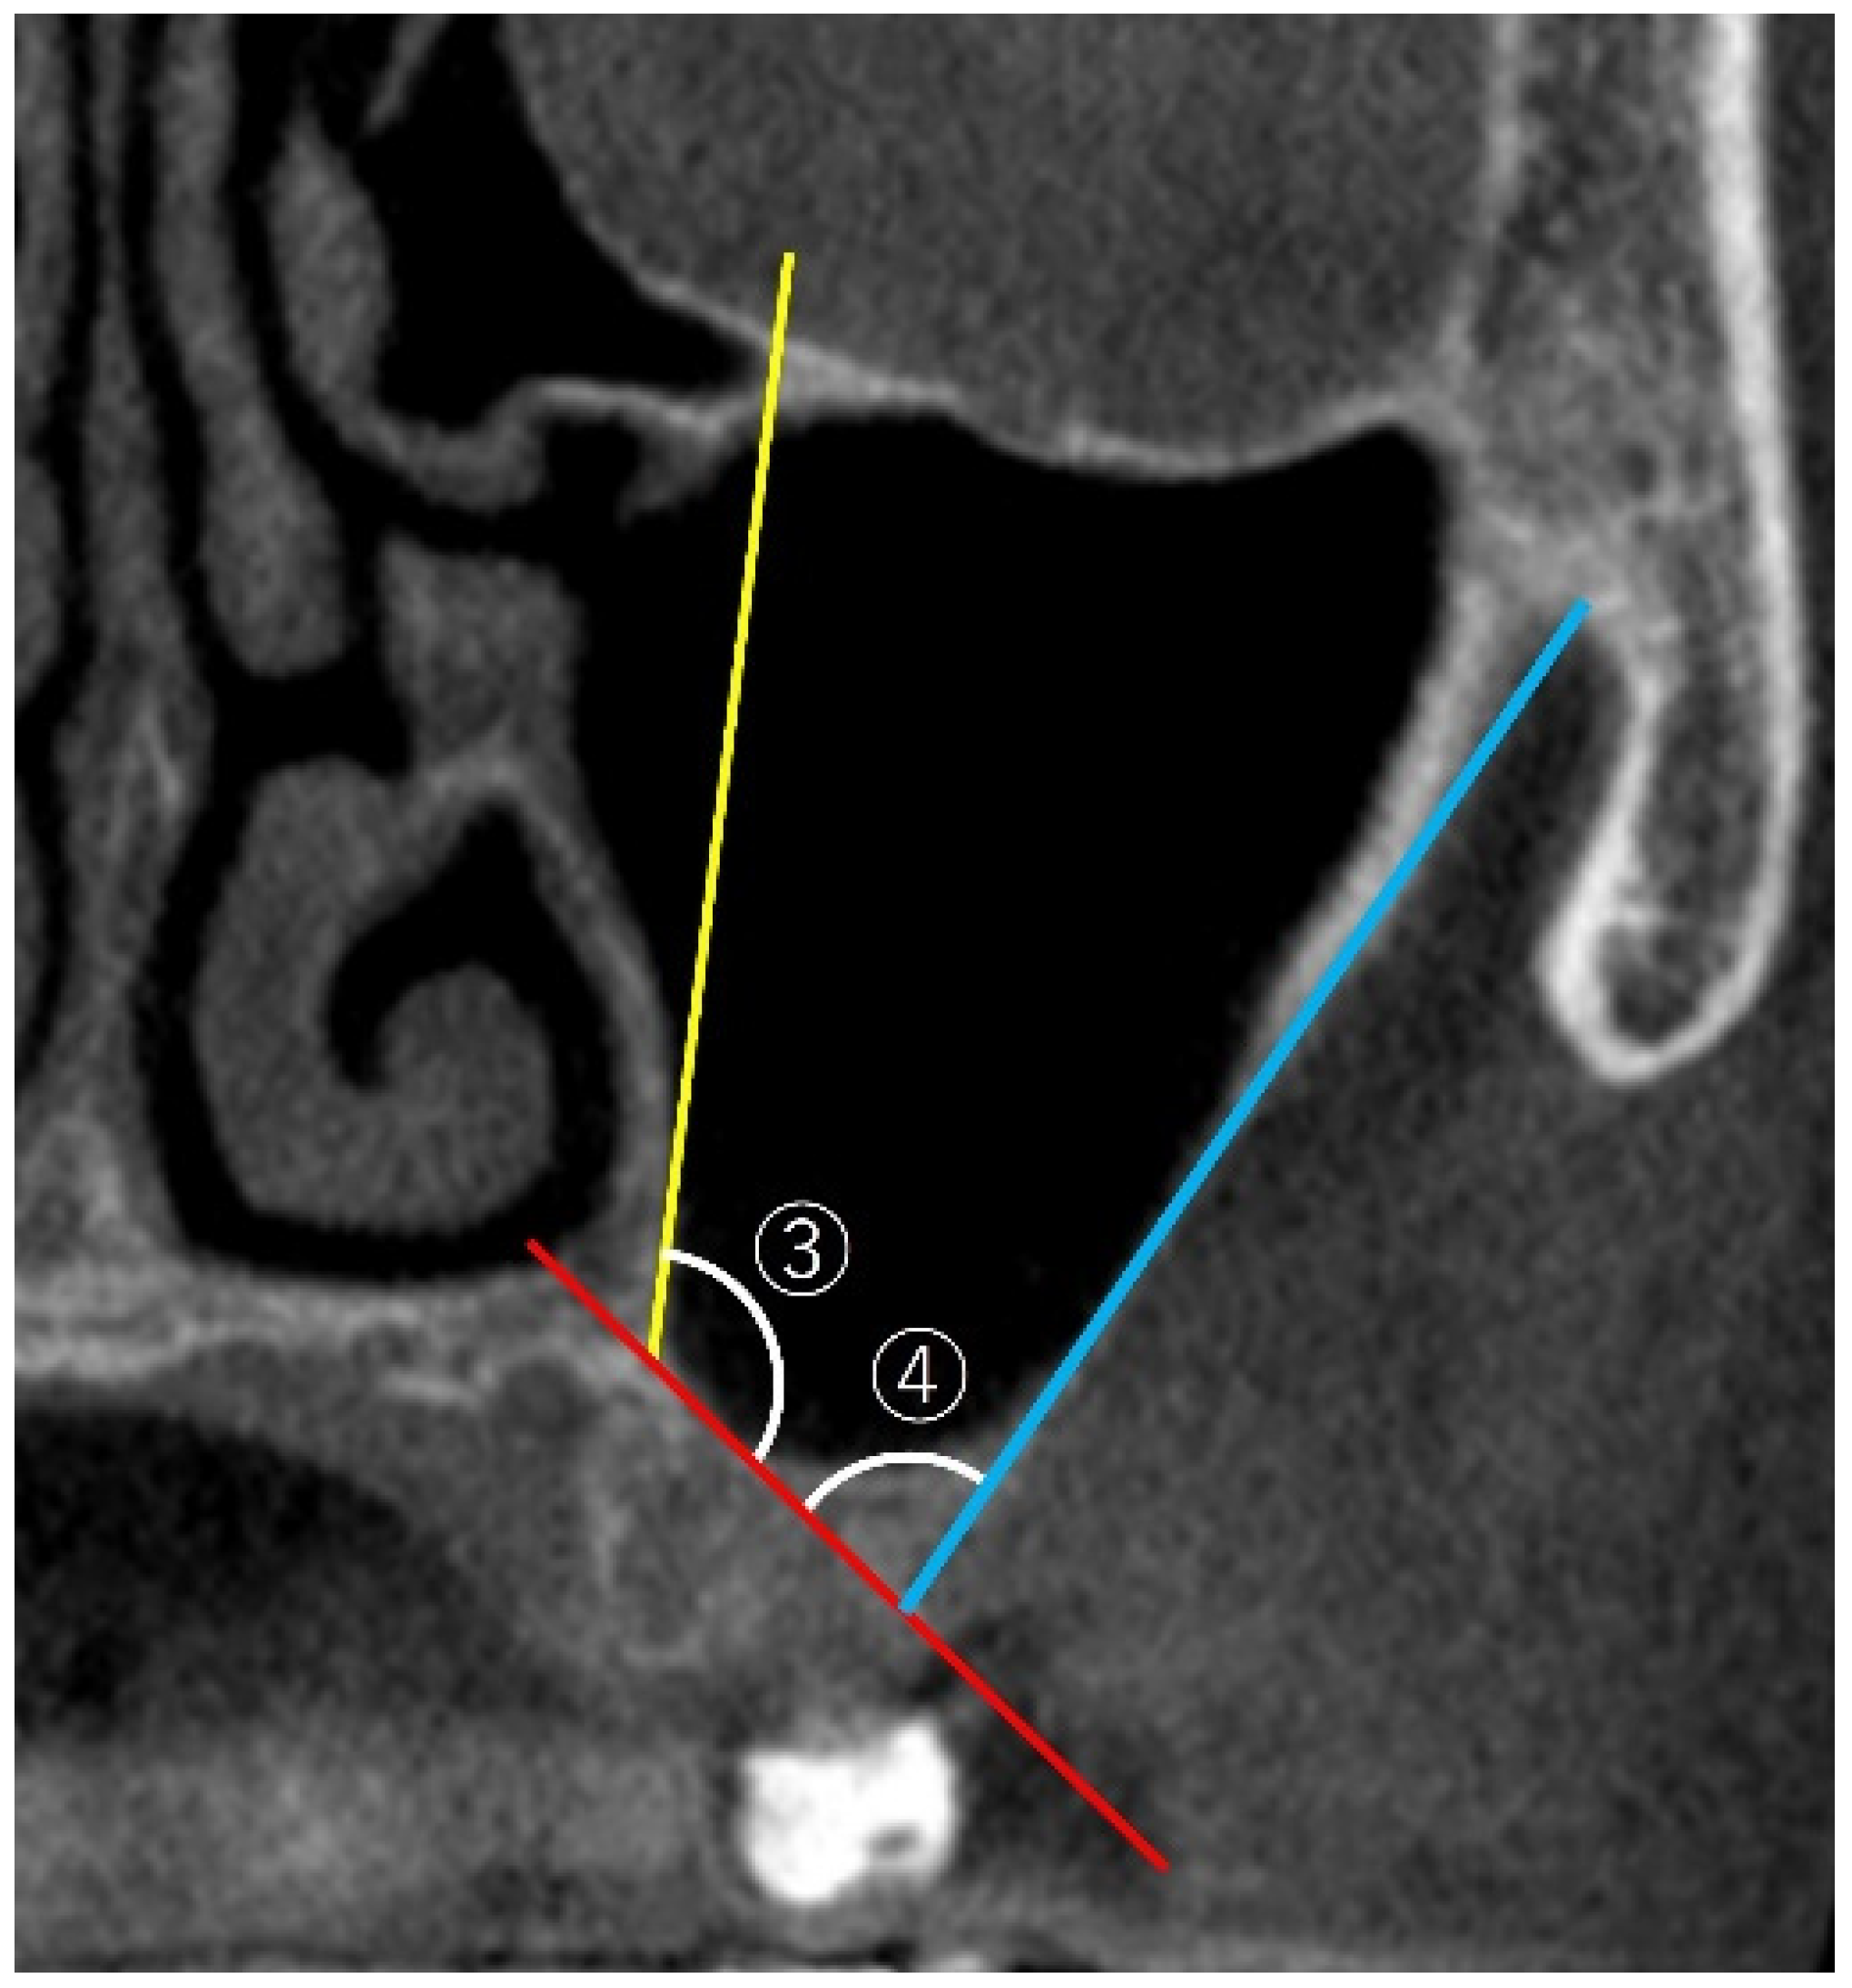

2.3.2. Measurement of PNR Angle and Maxillary Sinus Angle (MSA)

2.3.3. Measurement of Sinus Membrane Thickness (SMT)